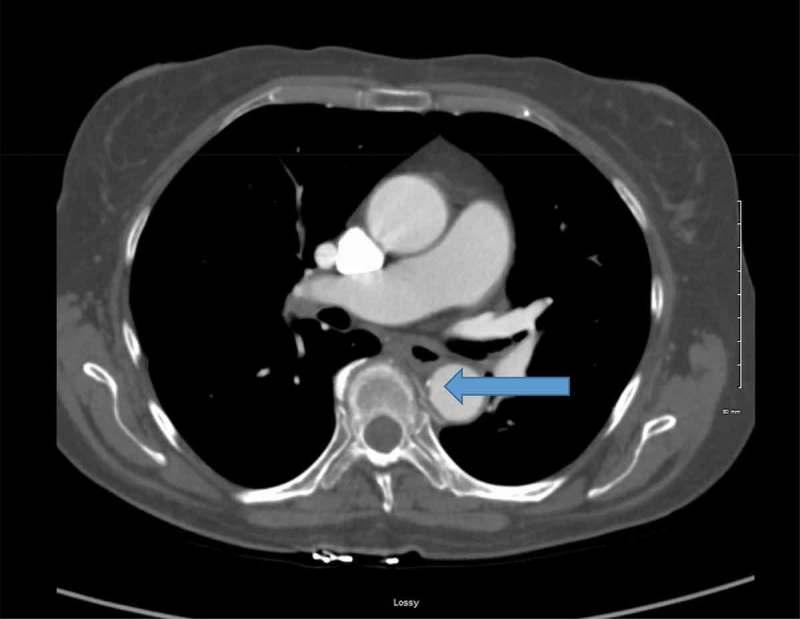

偶然发现的降主动脉血栓:药物治疗与手术治疗的难题

Incidental descending thoracic aortic thrombus: the conundrum of medical versus surgical therapy.

: A mural thrombus in the descending thoracic aorta frequently leads to distal organ and acute limb ischemia, increasing overall morbidity and mortality. Early diagnosis is imperative as thrombi are usually discovered after end organ damage has taken place. The formation of a mural thrombus in descending aorta has not been fully explained; however, the principle of Virchow's triad for thrombogenesis (hypercoagulability, stasis of blood flow and endothelial injury) remains the likely pathophysiologic mechanism. : We present a case of a descending aortic thrombus incidentally detected on computed tomography scan in a 65-year-old female and successfully treated with anticoagulation, preventing subsequent complications. : Suspicion for an aortic thrombus should arise when the origin is not known for acute onset distal limb or organ ischemia.

摘要

降主动脉壁内血栓常导致远端器官和急性肢体缺血,增加总体发病率和死亡率。由于血栓通常在终末器官损伤发生后才被发现,因此早期诊断至关重要。降主动脉壁内血栓的形成尚未完全阐明;然而,血栓形成的魏尔啸三要素(高凝状态、血流淤滞和内皮损伤)原则仍是可能的病理生理机制。我们报告一例65岁女性在计算机断层扫描中偶然发现降主动脉血栓,并通过抗凝治疗成功治愈,预防了后续并发症。当急性发作的远端肢体或器官缺血原因不明时,应怀疑主动脉血栓形成。